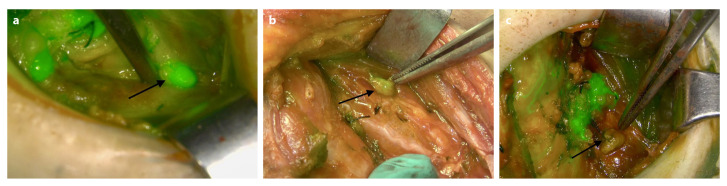

Abstract Image